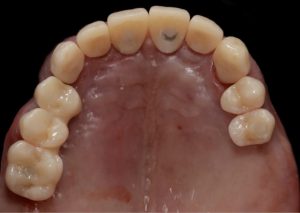

Healing abutments were removed and (b) the second set of temporary restorations was paced. Fig. 17 (i,ii)

Immediate post-operative view of the inserted provisionals. Fig. 19 (i,ii)